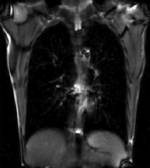

| fixed image/target | moving image |

| |

| unregistered moving series | moving input after registration (only frames 1-27 shown) |